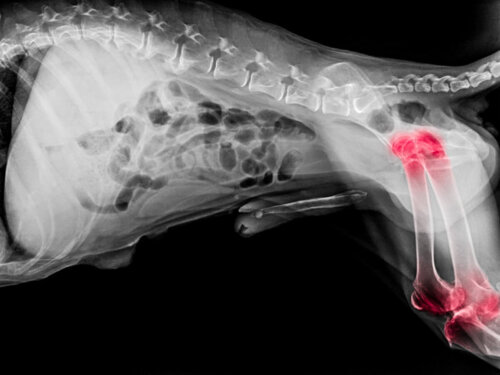

Hvordan diagnosticeres gigt og slidgigt hos hunde?

Diagnosen af gigt og slidgigt hos hunde er kompliceret, da der ikke findes nogen ufejlbarlig måde at påvise dem på. Dyrlægen skal gøre brug af hundens sygehistorie og fysiske tests , hvormed de vil forsøge at identificere sygdommens sværhedsgrad og type.

I tilfælde, hvor der er mistanke om infektion, vil der desuden blive taget prøver til analyse.